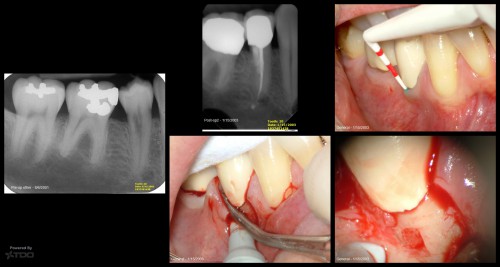

Accretions

By Gary Carr / August 1, 2018

When a biofilm attaches to root cementum, it can undergo a calcification process very similar […]